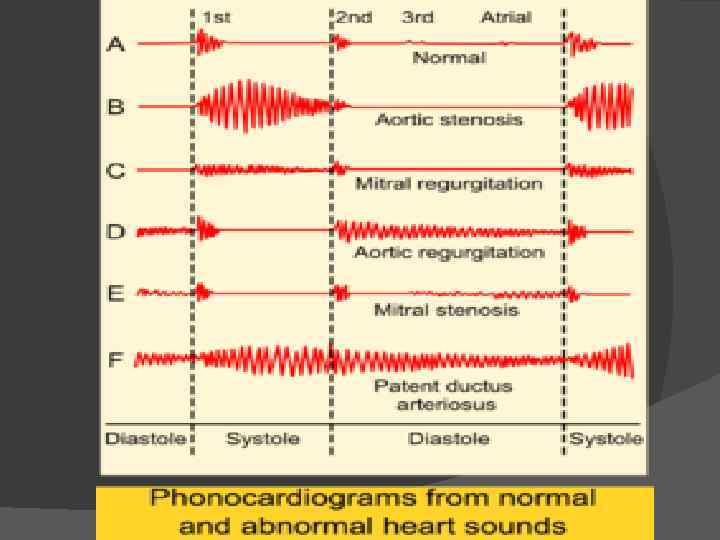

Пульс быстрый, высокий, неравномерность наполнения на обеих руках. Ослабление пульсации на левой руке связано с анатомическими особенностями: отверстие левой подключичной артерии располагается напротив отверстия артериального кровотока, и сброс крови через проток значительно сказывается на ее кровенаполнении. Наиболее характерный и важный диагностический признак при этом пороке - своеобразный систоло-диастолический шум, который появляется вслед за I тоном, нарастает по направлению ко II тону, а затем убывает в диастоле.

непрерывный систоло-диастолический шум достигает максимальной интенсивности в I-II межреберьях слева от края грудины. Шум обычно усиливается в горизонтальном положении больного, особенно резко - при сдавлении брюшной аорты вследствие повышения давления в ней. Он усиливается также при вдохе, благодаря увеличению количества крови, протекающей через артериальный проток (вследствие снижения давления в малом кругу). При выдохе шум ослабевает. Распространение шума ограничено, причем систолический компонент обладает большей проводимостью, чем диастолический. Шум распространяется на сосуды шеи, к левой ключице, в яремную ямку, меньше - в межлопаточное пространство. Значительно уменьшается' он по направлению к верхушке сердца и в подмышечную область. Не всегда можно выделить I и II сердечные тоны из сплошного систоло-диастолического шума.